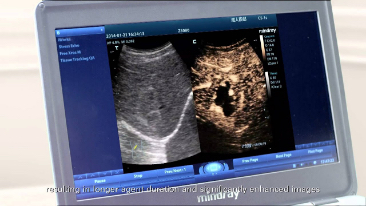

Echo Boost?

Teknologi pemrosesan sinyal adaptif Mindray yang unik dengan deteksi gema pintar, dirancang agar menggunakan informasi sinyal-ke-noise asli untuk menyempurnakan sinyal gema yang lemah sekaligus mengurangi suara bising di sekitar. Dengan demikian, dapat dihasilkan kecerahan gambar yang lebih seimbang dan visualisasi lapisan jaringan miokardium yang lebih baik.